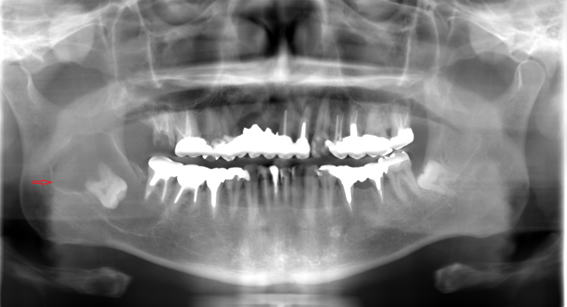

45歳男性 エナメル上皮腫